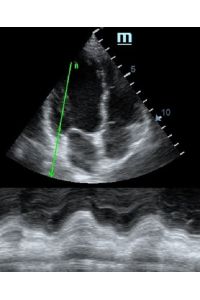

Но как же провести стандартные измерения в М-режиме, если мы его не использовали? На помощь приходит функция Free Xros M – анатомический М-режим. Имея записанную в память прибора видео петлю, мы можем провести линию М-режима в любом месте, при этом корректируя изначально не оптимальный угол.

Возможности применения функции многогранны: от измерения толщины стенок левого желудочка, движения створок митрального клапана и кооптации нижней полой вены до оценки сократимости миокарда как глобально, так и по сегментам.

TAPSE - показатель амплитуды движения латеральной части кольца трикуспидального клапана, позволяет количественно и быстро оценить систолическую функцию правого желудочка, норма которого составляет более 17 мм. Главным условием является проведение линии М-режима параллельно стенке правого желудочка в апикальном четырех камерном сечении, что легко достигается при Free Xros.